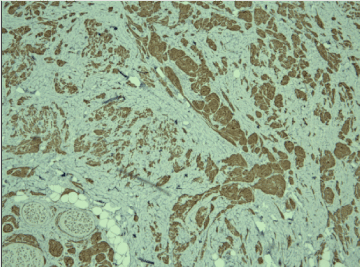

A frozen section was performed during surgery and the result was “invasive tumor, suspicious for malignancy”. Radical left mastectomy was performed with axillary lymph nodes dissection. The histological examination of the symptomatic lesion (11 mm) revealed a tumor, composed of nests of epitheloid tumor cells with monomorphous nuclei with occasional nucleoli, areas with spindle tumor cells in a fibrous background with hyaline change, areas with mature adipocytes. Peripheral nerves were surrounded by tumor nests (Figure 1). Scattered lymphocytic infiltrates were also found. PAS reaction revealed single positive granules in a few tumor cells (Figure 2). The described histological findings are observed in both mammary MFB and granular cell myoblastoma. Immunohistochemical analysis was performed. The tumor cells were positive for: S-100 protein (Figure 3), CD68 (Figure 4), Vimentin (Figure 5). The proliferative index detected with Ki67 is low (1-2%) (Figure 6). The tumor cells were negative for ER, PR and HER. The histological examination of the dissected lymph nodes revealed sinus histiocytosis, follicular hyperplasia and lipomatosis. Metastases were not found.

Figure 5. Positive cytoplasmic reaction for CD68 in tumor cells, x20